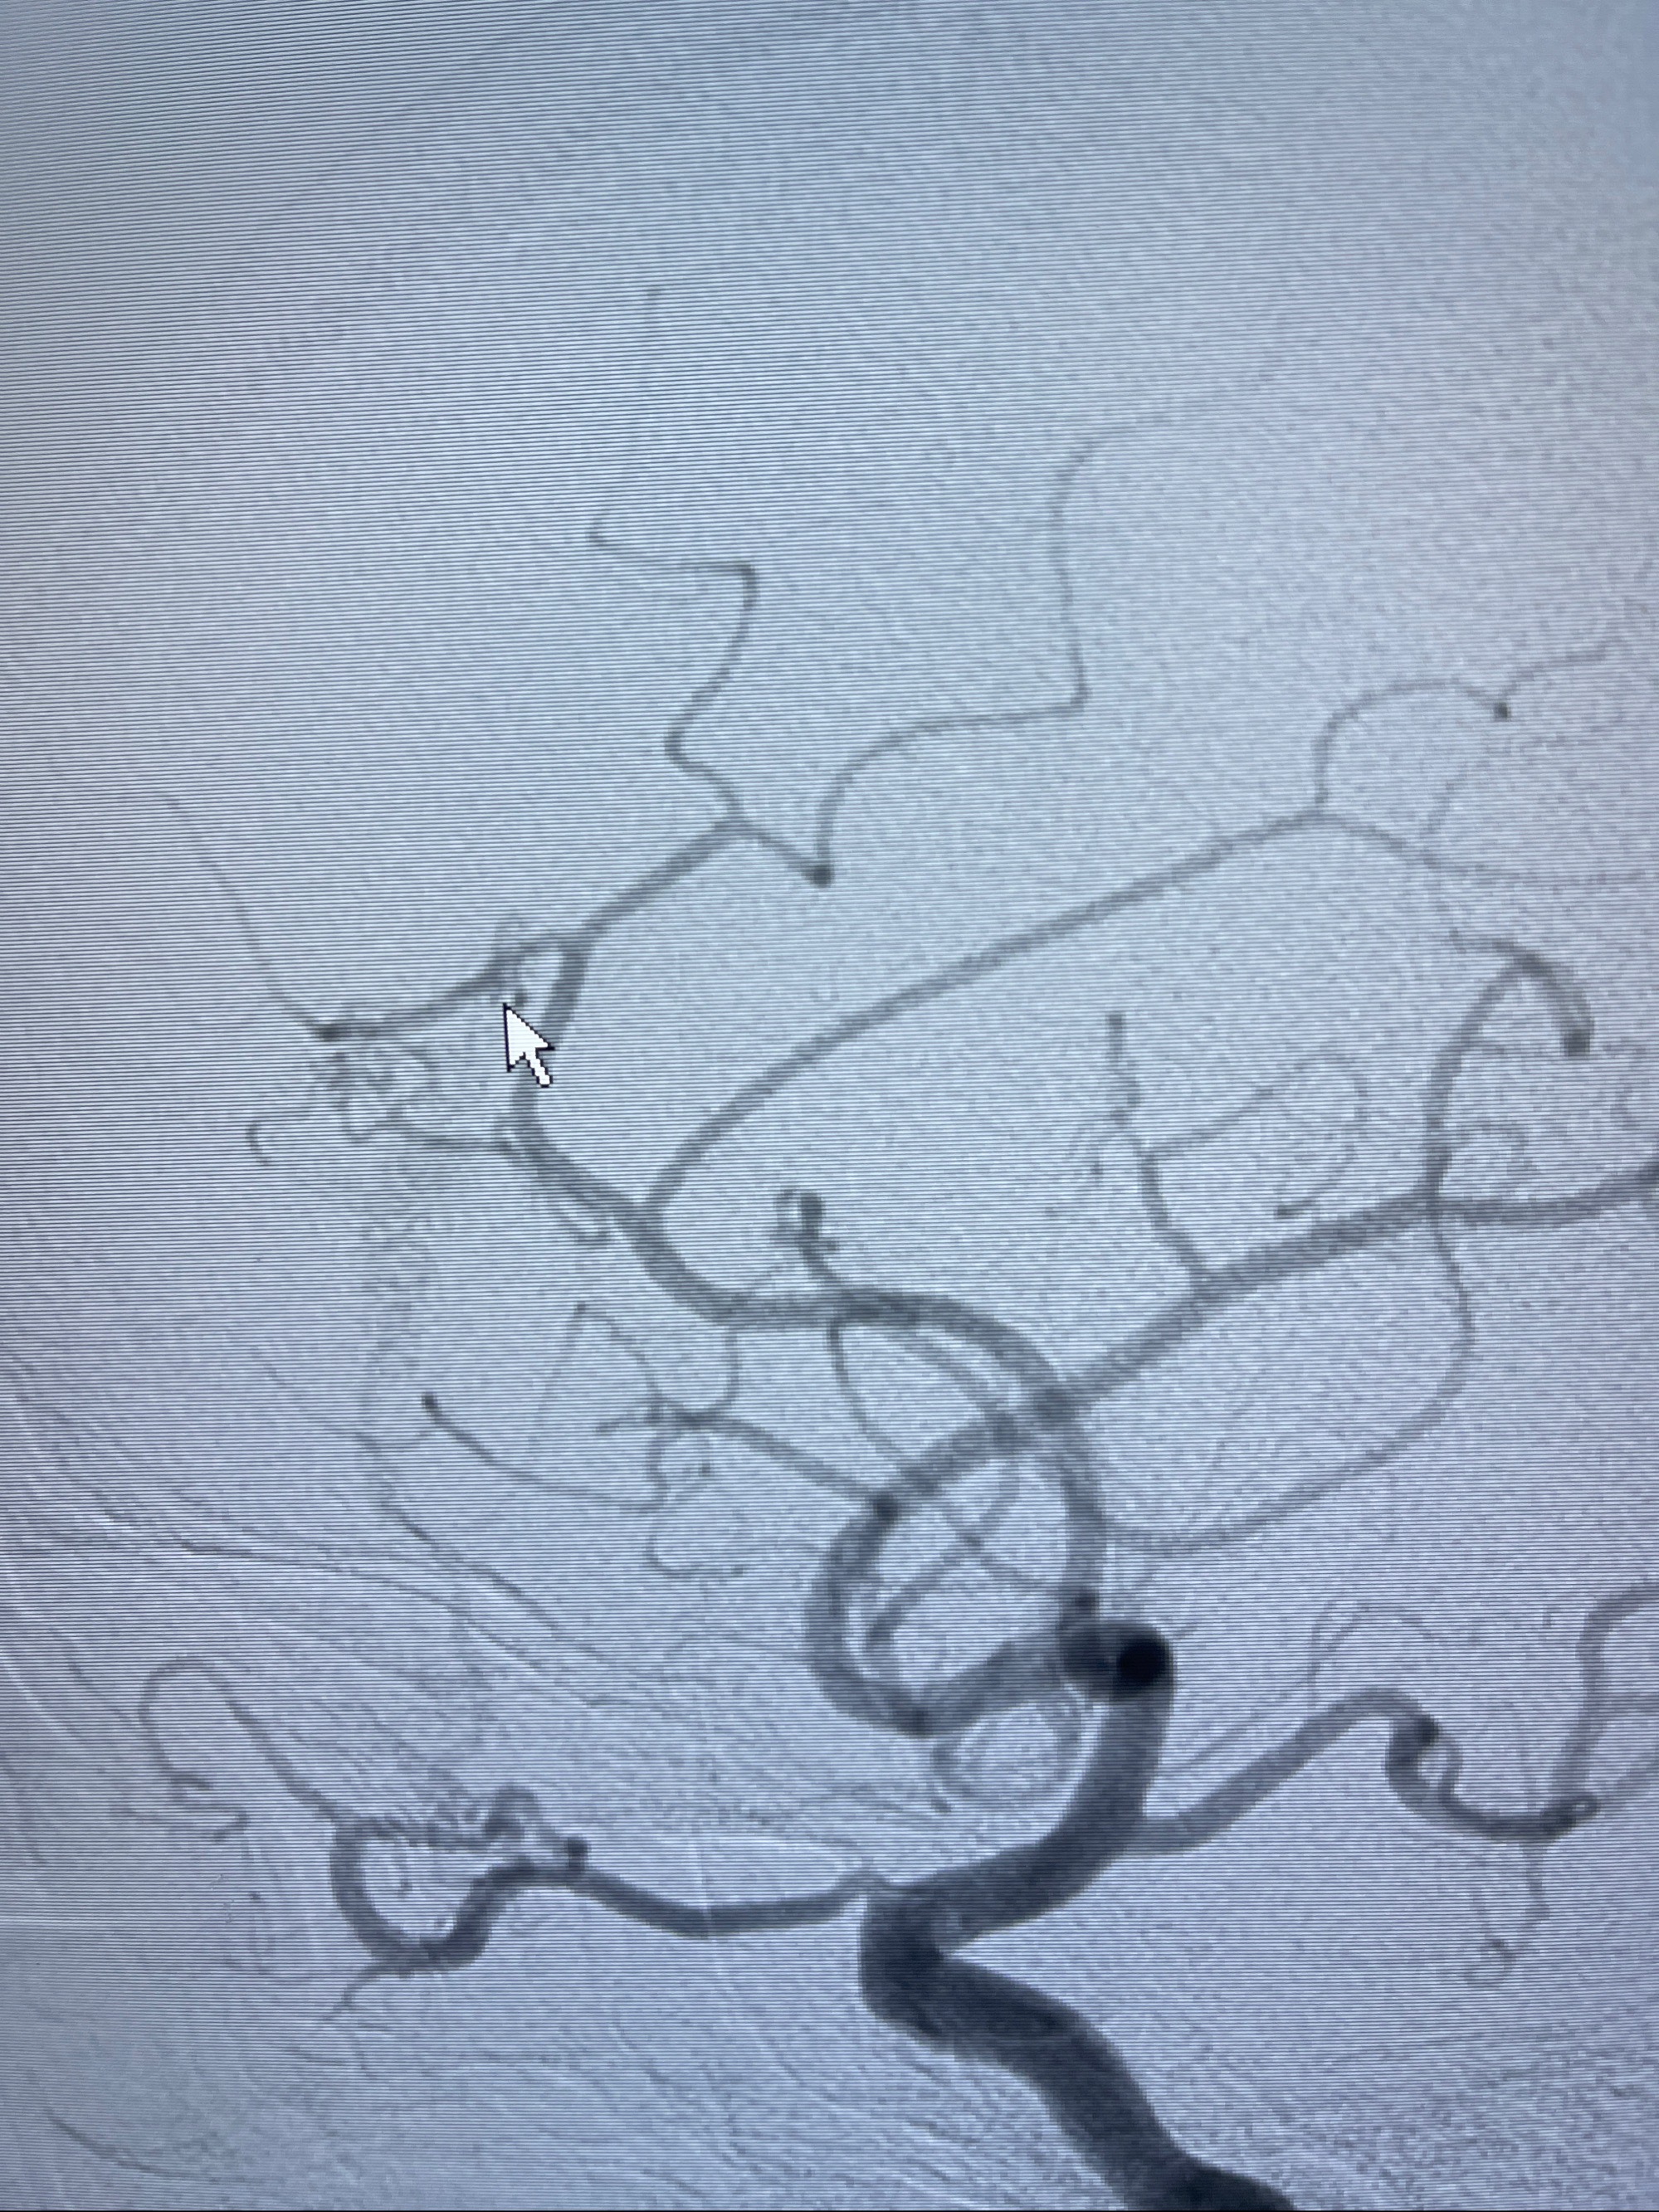

2023年8月21日]景德镇市第一人民医院脑血管造影检查,提示:主动脉弓、双侧颈总动脉、锁骨下动脉造影未见异常,左侧大脑前动脉静脉瘘。

2023-09-13全脑血管造影:前颅底硬脑膜动静脉瘘,供血动脉为双侧胼周动脉、眼动脉脑膜支,静脉向上矢状窦方向引流